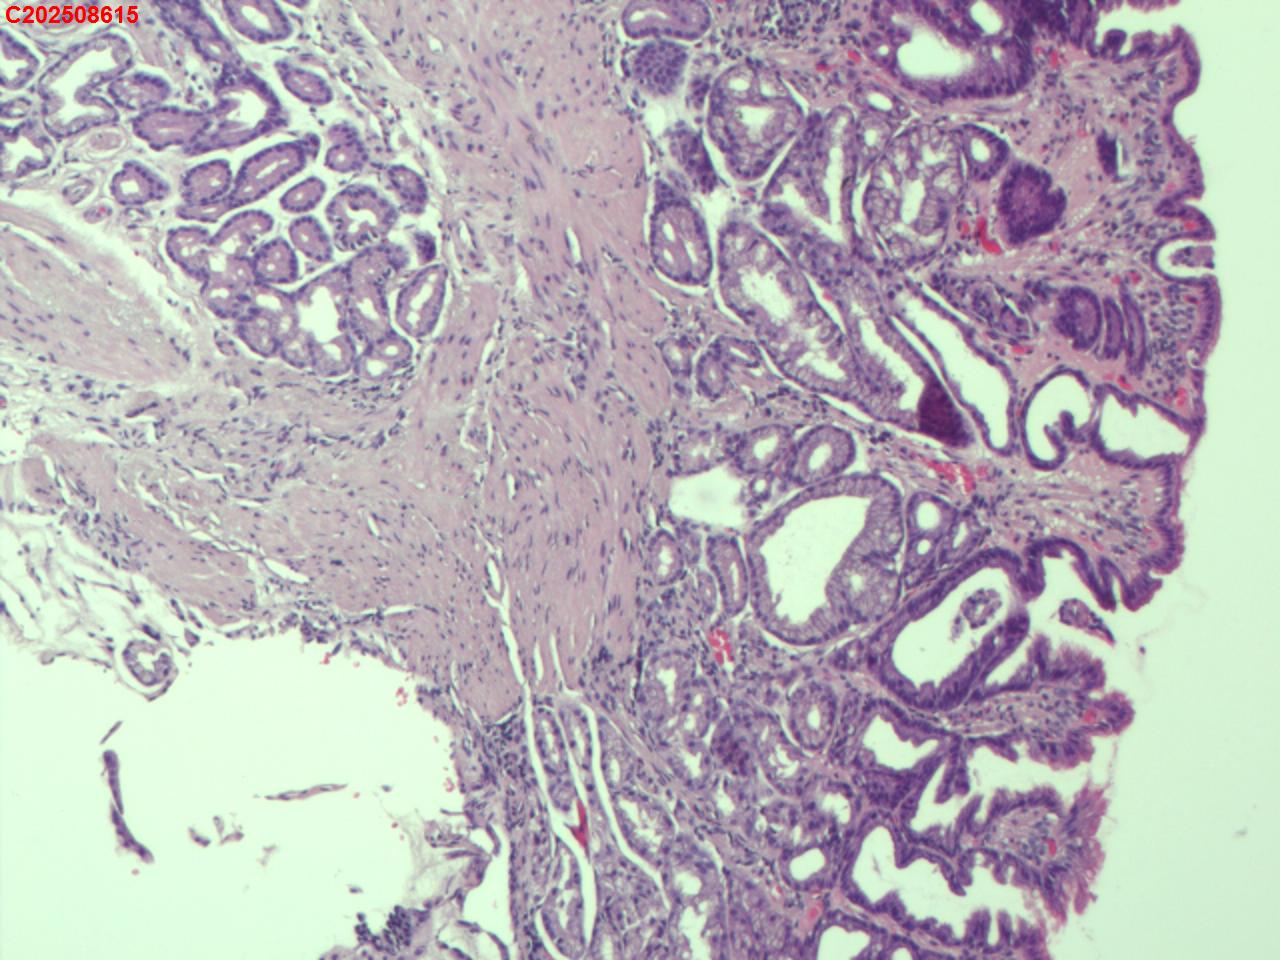

吻合口粘膜

性别

男

年龄

73岁

临床诊断

胃息肉、吻合口炎

一般病史

胃切除术后

标本名称

大体所见

吻合口处可见一枚直径约4mm息肉样隆起。

息肉样增生

这个形态如果在吻合口,可以考虑息肉样囊性胃炎。